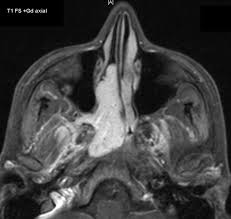

Fibroma nasofaríngeo juvenil. También conocido como Fibroangioma juvenil es un tumor vascular que afecta casi exclusivamente la nasofaringe de adolescentes de sexo masculino. Su manejo es complejo dada su naturaleza vascular y sus frecuentes recurrencias.

Los fibromas pueden ser sésiles, pero lo más corriente es que sean pediculados. Alcanzan a menudo un gran tamaño y muchas veces son asiento de procesos inflamatorios; en consecuencia, las adherencias a las estructuras adyacentes son frecuentes. El aporte sanguíneo adicional deriva de estas adherencias. Estos fibromas no producen metástasis, sino que crecen por propagación. Pueden invadir la órbita, los senos accesorios, las fosas pterigoidea y temporal, o la cavidad intracraneal.

Los síntomas mencionados aumentan de intensidad a medida que progresa la neoformación, hasta que la reabsorción de tejido óseo es considerable, excepto en el caso de que el tumor se propague por debajo de las cavidades nasal y faríngea, así como en el interior de la cavidad craneal. En este caso no es tan acentuada la necrosis compresiva del tejido óseo. La exploración revela que el tumor está formado por una masa redondeada de coloración rosada o purpúrea oscura. Las venas presentan, con frecuencia, un aspecto varicoso, por lo que la exploración digital o con instrumentos debe ser realizada cuidadosamente para evitar su lesión. La neoformación puede proyectarse en las ventanas nasales posteriores, o dirigirse hacia el antro o a los otros senos.